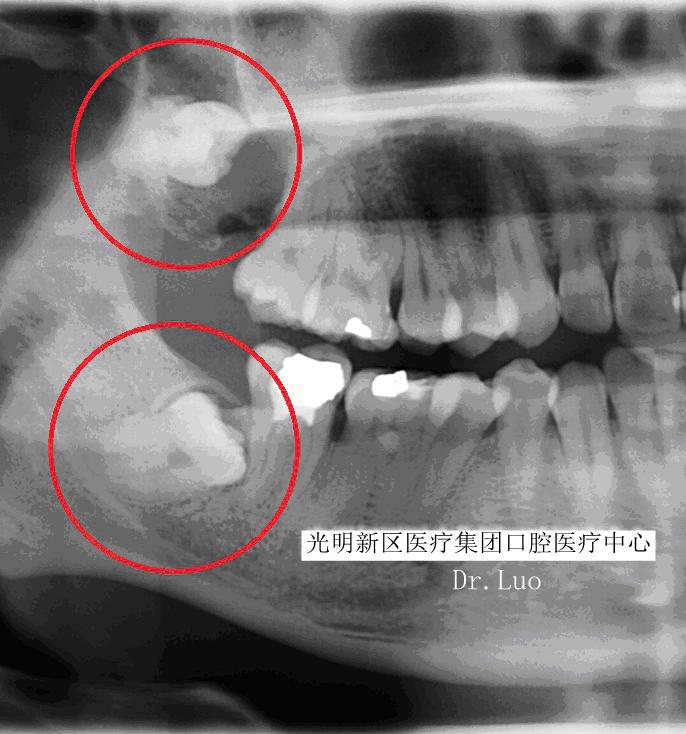

智齿,指的是人类口腔内牙槽骨上最里面的第三颗磨牙,从正中的门牙往里数刚好是第八颗牙齿。由于它萌出时间很晚,一般在16~25岁间萌出,此时人的生理、心理发育都接近成熟,有“智慧到来”的象征,因此被俗称为“智齿”。

而“阻生”智齿是之那些由于邻牙、骨或软组织阻碍而只能部分萌出或完全不能萌出,且以后也不能萌出的第三磨牙。

那么阻生智齿有什么危害呢?

1)上、下后牙反复肿痛:

有时候智齿出现了,却依旧发生局部肿痛,严重的时候甚至可以让整个半侧脸颊肿的像个水球,这种情况就是冠周炎,是指整个牙冠周围发生了炎症。

由于智齿(特别是下颌的)周围特殊的解剖结构,炎症常常会侵袭到周围间隙组织,造成如最常见的半侧面颊的肿胀。如果炎症侵袭的下颌后部的间隙组织,造成喉头水肿、气道压迫,那么威胁生命不是危言耸听。

2)龋坏:

由于智齿本身生长位置就比较靠后,清洁起来有一定难度,所以蛀牙情况很普遍,有些智齿不甘寂寞自己蛀牙,还会把前牙累及。

3)塞牙:

很多时候智齿的生长会和前牙形成一个夹角,形成一个空间。食物往往会嵌塞其中,让您感到不适。长期的食物嵌塞不光会造成牙龈的红肿、退缩,甚至可以是牙槽骨吸收,形成恶性循环,加重食物嵌塞。

4)根、骨吸收:

由于智齿生长持续的压力压迫,造成邻近牙齿、骨质的吸收。可导致邻牙不适、疼痛甚至松动脱落。

5)牙源性囊肿、肿瘤:

长期的炎症、压迫周围组织可能导致颌骨囊肿、牙源性肿瘤的产生。不仅可能造成邻牙的松动脱落,还可能引起下颌神经的损伤、颌骨的病理性骨折,甚至有肿瘤后癌变的可能。

6)拥挤:

智齿生长带来的持续性挤压可能是造成您牙齿不齐的重大原因。

7)下颌关节紊乱:

由于智齿临近咀嚼肌群,所以它有点风吹草动直接会影响到咀嚼肌。肌肉收到压迫而痉挛,最重可造成完全张不开嘴,又称“牙关紧闭”。

阻生智齿的罪过如此之多,引起的疾病如此棘手,所以面对阻生智齿,面对这个不定时的*弹炸**我们必须毫不手软,坚决予以铲除——尽快拔除。